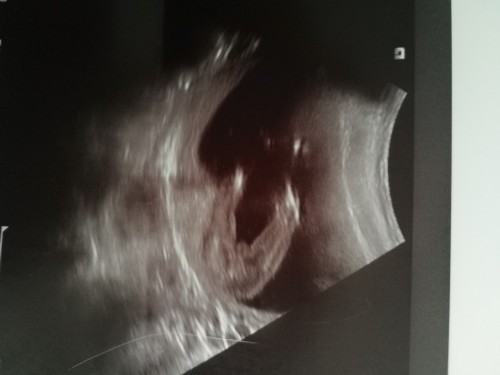

ชายหรือหญิงคะ

หมอบอกไม่แน่ใจใจว่าเป็นแคมหรือไข่😬🤣

ไข่ค่ะ ผู้ชายแน่ๆจ้าาา ทางนี้ได้ลูกชายก็ภาพซาวด์แบบนี้เลยจ้า😂

ทางนี้หมอบอกว่า ญ ค่ะเป็นกลีบๆ อันนี้ตอน 5เดือนไม่รู้ใช่ป่าวค่ะ 😂

แบบนี้ไข่แน่ๆค่ะ😅😅

น่าจะลูกชายนะคะ

คล้ายไข่เลยนะคะ

ผู้ชายคะ คุณแม่

น่าจะไข่นะคะ

น่าจะชายค่ะ